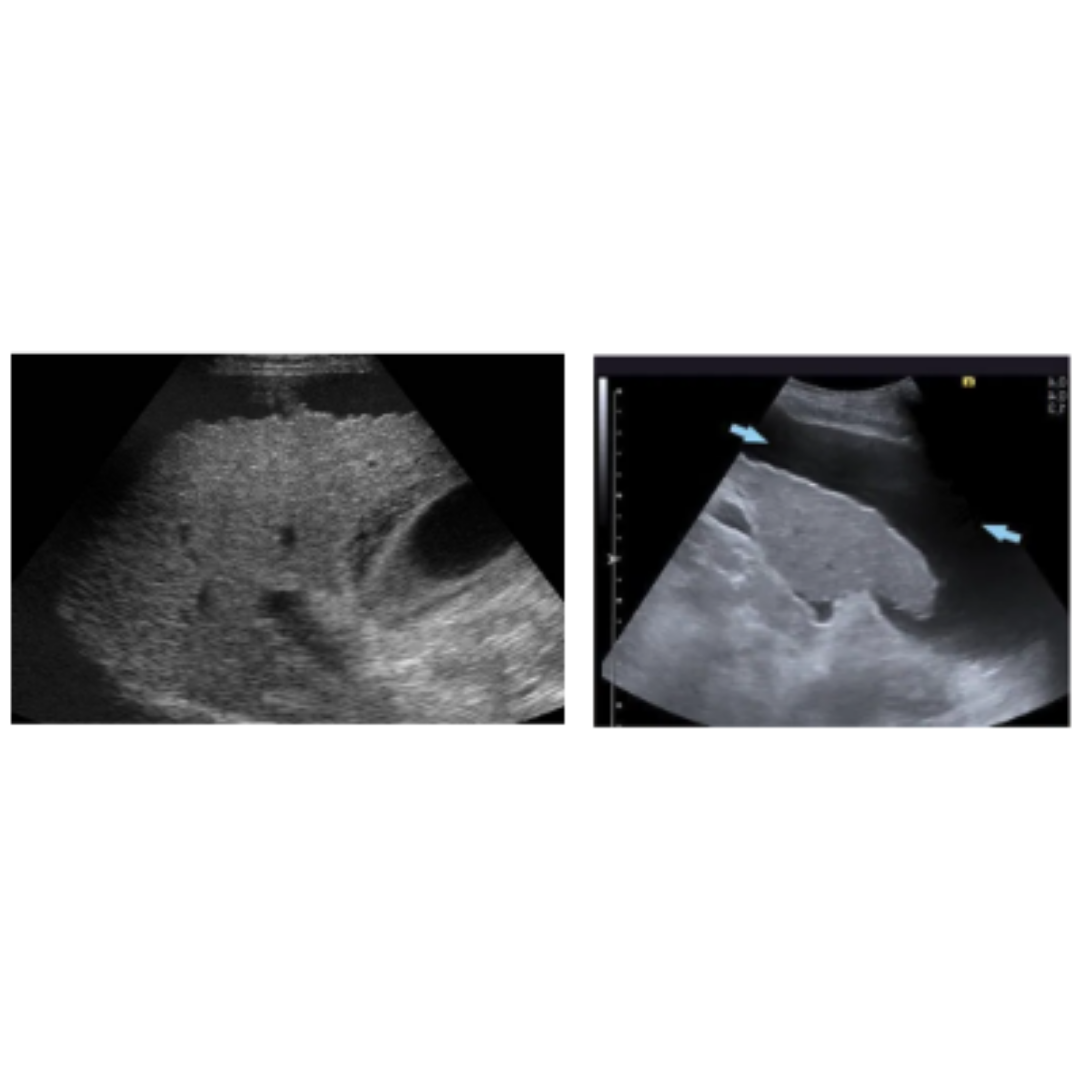

Figura 5: Aumento de ecogenicidad del parénquima hepático.

Complicaciones DHC